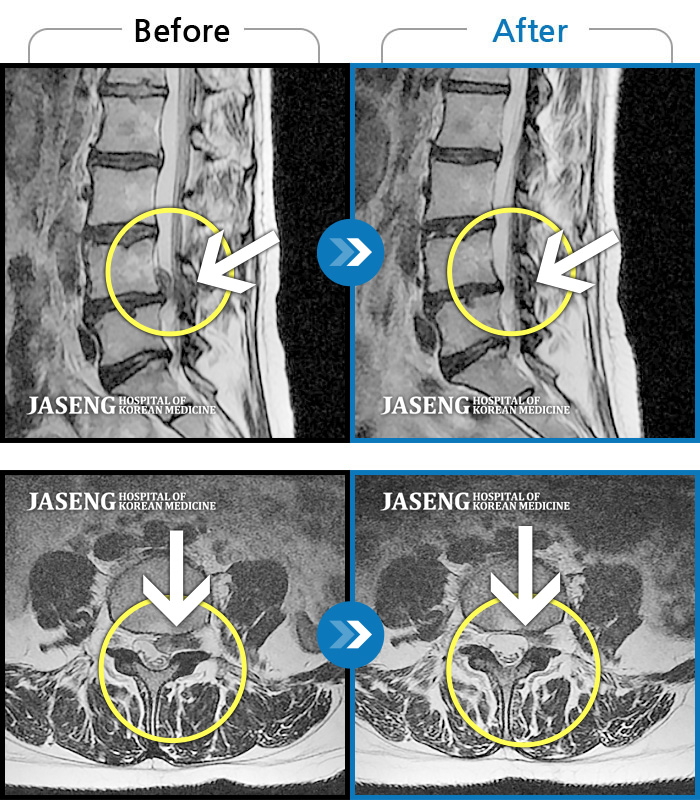

Before

After

환자에게 사전 동의를 받아 동일 조건에서 촬영되었습니다.

개인에 따라 치료 후 부작용이 발생할 수 있으니 의료진과 상담 후 치료를 진행하시기 바랍니다.